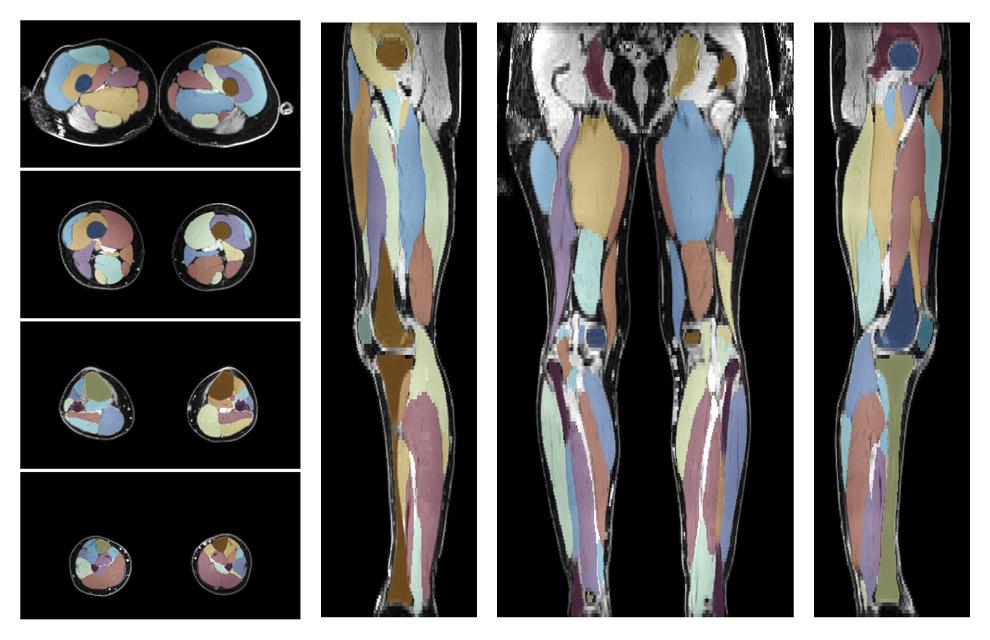

• Automated muscle and bone segmentation.

Overlay of automated muscle segmentation labels on dixon water image.